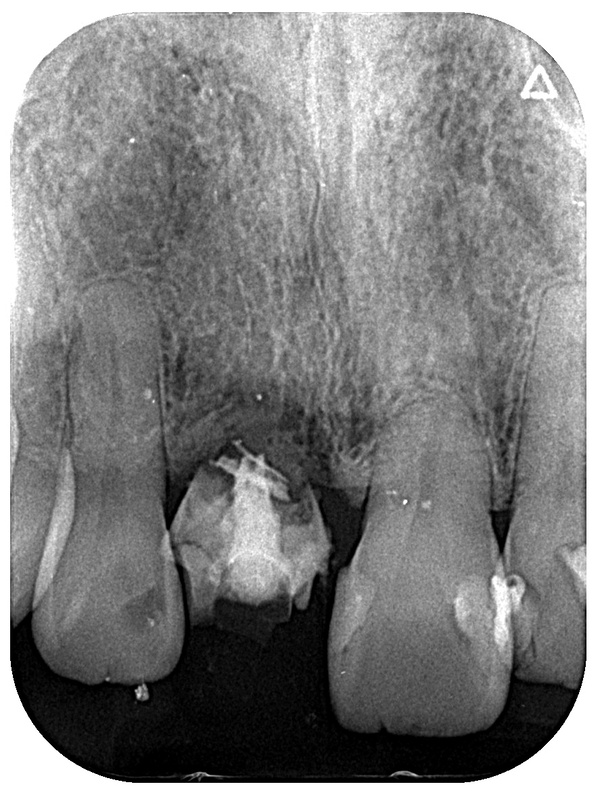

まずはレントゲン写真の撮影や歯周病の検査を行い、下記の3つの治療方法の説明・提案を行いました。

今回のケースでは、以下の写真のように左上1番目の歯の根っこが極端に短かったため、長期的な安定は見込めませんでした。